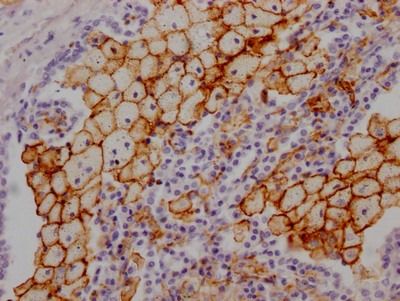

IHC image of CSB-RA268157A0HU diluted at 1:100 and staining in paraffin-embedded human lung tissue performed on a Leica BondTM system. After dewaxing and hydration, antigen retrieval was mediated by high pressure in a citrate buffer (pH 6.0). Section was blocked with 10% normal goat serum 30min at RT. Then primary antibody (1% BSA) was incubated at 4℃ overnight. The primary is detected by a Goat anti-rabbit IgG polymer labeled by HRP and visualized using 0.05% DAB.

IHC image of CSB-RA268157A0HU diluted at 1:100 and staining in paraffin-embedded human kidney tissue performed on a Leica BondTM system. After dewaxing and hydration, antigen retrieval was mediated by high pressure in a citrate buffer (pH 6.0). Section was blocked with 10% normal goat serum 30min at RT. Then primary antibody (1% BSA) was incubated at 4℃ overnight. The primary is detected by a Goat anti-rabbit IgG polymer labeled by HRP and visualized using 0.05% DAB.